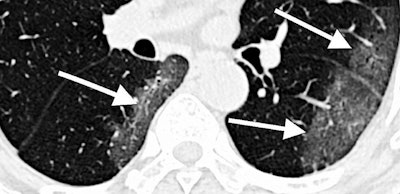

CT scan of lungs of COVID-19 patient with areas described by radiologists as resembling grains of ground glass. Image courtesy of RSNA.The RSNA led the charge surrounding COVID-19 images and released the initial set of such images through its RSNA International COVID-19 Open Radiology Database (RICORD). The society is currently processing additional contributions, and it has also partnered with the Society of Thoracic Radiology to source 120 CT scans from four international sites.